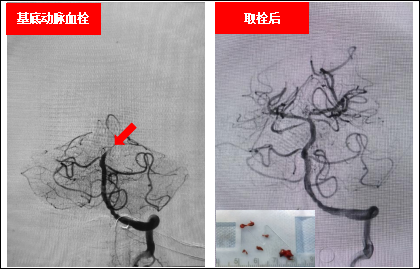

基底动脉闭塞患者接受机械取栓治疗前后对比图